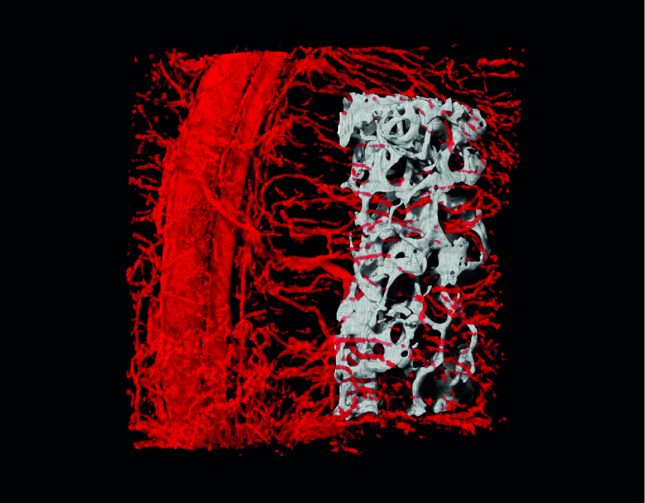

לאחרונה פותחה בטכניון טכנולוגיה המאפשרת לגדל במעבדה רקמת עצם המרושתת בכלי דם, המאיצה את היקלטות הרקמה המהונדסת באיבר הפגוע. החוקרים בפקולטה להנדסה ביו-רפואית בטכניון הציגו בכתב העת Advanced Functional Materials הצלחה ביצירת רקמת עצם המכילה רשת כלי דם. בניסוי בחולדות נקלט שתל הרקמה בהצלחה בעצם הפגועה. את המחקר הובילו פרופ' שולמית לבנברג וד"ר עידן רדנסקי.

יצירת כלי דם ברקמה מהונדסת היא אתגר קשה ממילא, אך היא קשה שבעתיים ברקמת עצם בשל צפיפותה וקשיחותה. הפתרון שפיתחו חוקרי הטכניון מבוסס על צימוד בין העצם לרקמה רכה השולחת לתוך העצם את כלי הדם. כדי לבחון את ישימות הטכנולוגיה בהיבט הקליני הושתלה העצם עם כלי הדם בגופה של חיית המודל ואכן, כלי הדם של העצם המושתלת התאחו עם כלי הדם של האיבר הפגוע, המתלה הוטמע ברקמת היעד ותוך שבועות ספורים הושגה החלמה מלאה.

"המחקר של עידן רדנסקי מבטא את השילוב הייחודי שהפקולטה מקדמת – שילוב בין הנדסה ורפואה," אומרת פרופ' לבנברג. "הוא רתם הבנה מעמיקה של תהליכים ביולוגיים, ואת כלל הידע שרכש בלימודי הכירורגיה ורפואת השיניים, לפיתוח של טכניקה חדשה לשיקום רקמות פגועות. היה כאן גם שיתוף פעולה חיוני ומועיל בין פקולטות שונות בטכניון, בין ישראל לחו"ל ובין אקדמיה לתעשייה: את שתלי העצם קיבלנו מפרופ' גורדנה ווניאק-נובקוביץ' שבאוניברסיטת קולומביה, ומומחי חברת Bruker-Skyscan סייעו לנו רבות בדימות כלי הדם המהונדסים ורקמת העצם בתוך הרקמות המתחדשות. שיתוף פעולה זה, עם הסיוע הנדיב של קרן המחקר האירופית (ERC) והקרן הלאומית למדע (ISF), אפשרו לנו לרשום את ההישג הזה, שאנו מתכוונים להמשיך ולפתח לטובת השתלה בבני אדם".